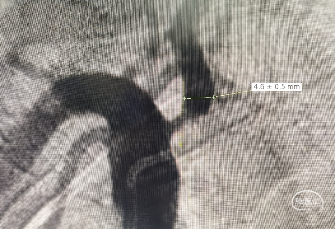

DSA提示右侧椎动脉起始段狭窄>75%。

DSA提示右侧颈内动脉起始段狭窄约90%。